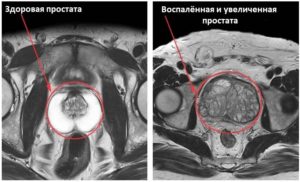

- Здоровая простата. Размеры железы, ее капсулы, семенников, окружающих тканей, сосудов, нервов — все в норме. Опухоли отсутствуют.

- Доброкачественная гиперплазия. На снимке МРТ видно симметричное или ассиметричное разрастание железы с сохранением равномерных контуров.

- Простатит. На МРТ видно, что железа становится крупнее, но ее контуры, в отличие от аденомы, нечеткие (из-за ослабления кровонаполнения от венозного сплетения).

- Рак на МРТ характеризуется единичными или множественными новообразованиями. Они локализуются точечно или распространяются за капсулу простаты.